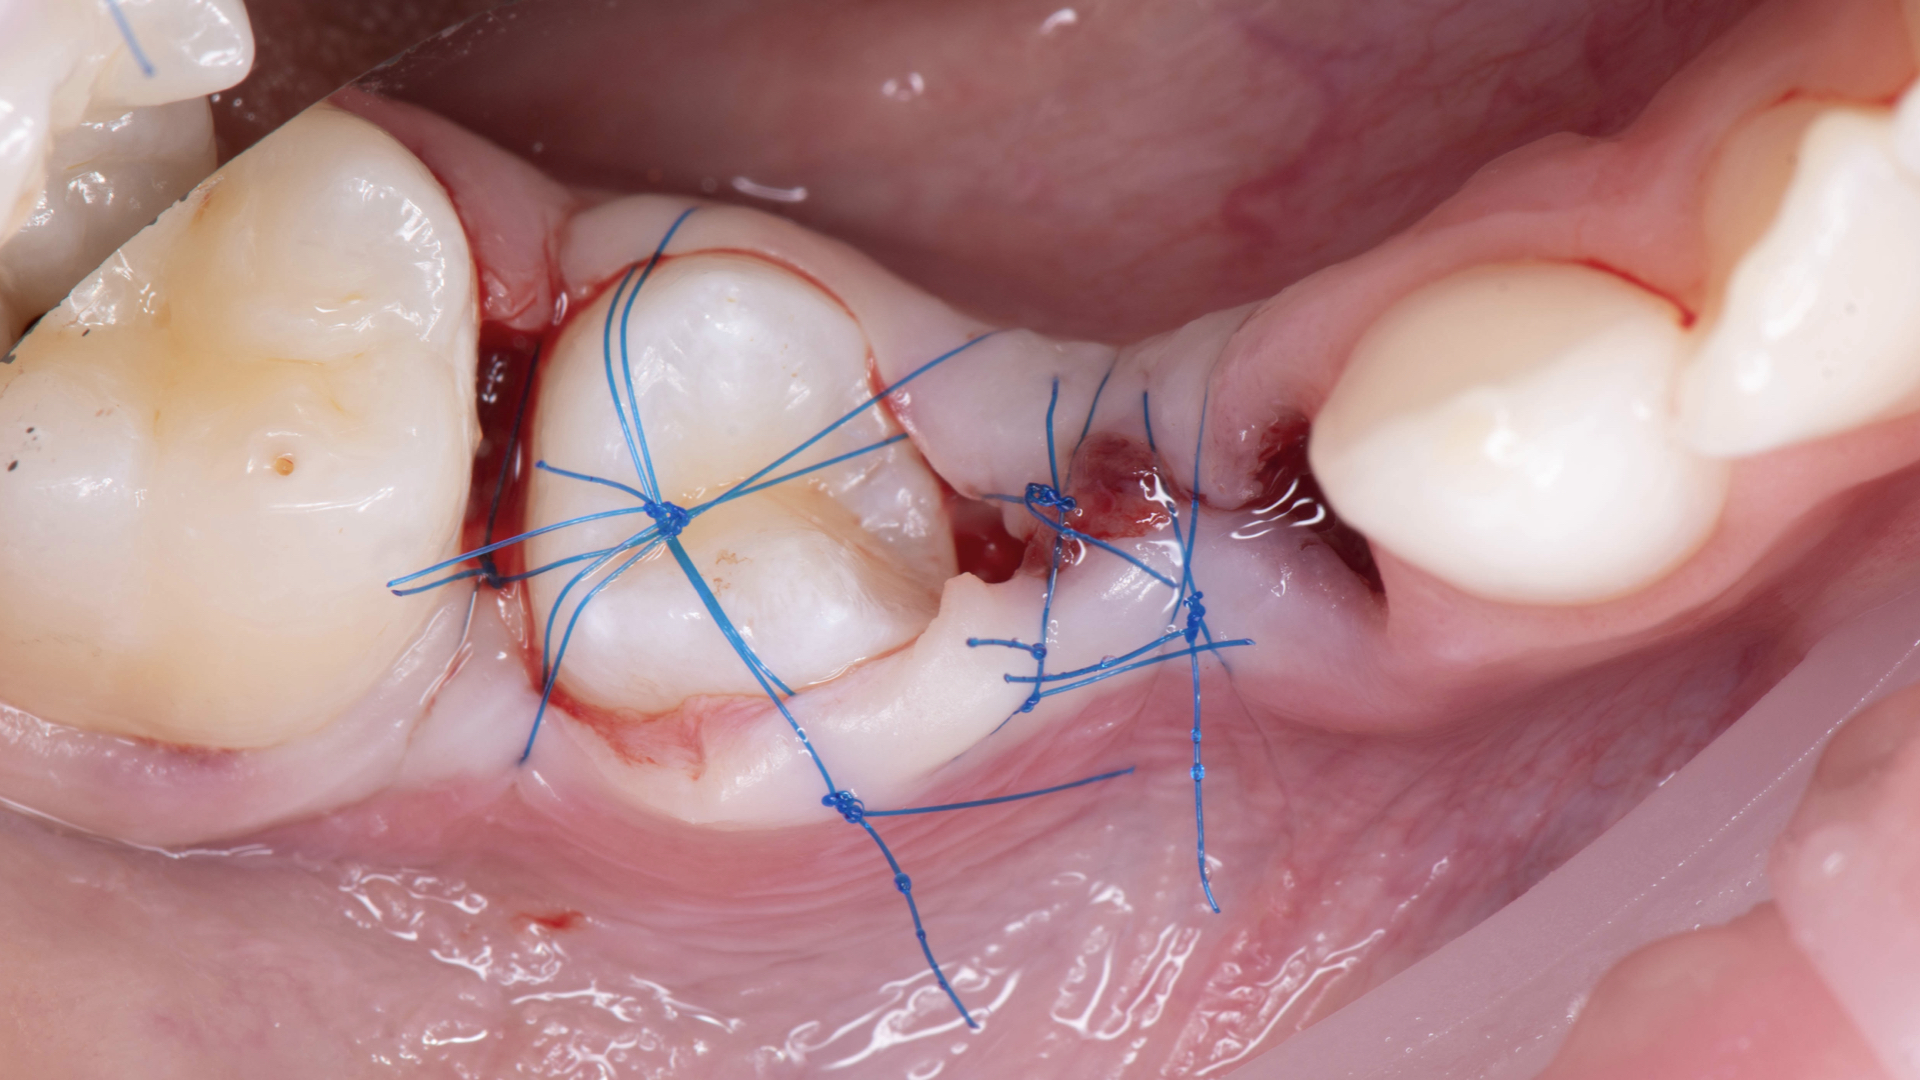

Autotransplantácia

Biologické a živé riešenie: Objavte silu parodontálnych vlákien v modernej stomatológii.

Prečo v dobe implantátov hovoriť o autotransplantácii? Pretože parodontálne ligamentá (PDL), propriocepcia a prirodzená remodelácia kosti sú benefity, ktoré nám žiadny umelý materiál nenahradí. Tento intenzívny kurz vás prevedie striktne evidence-based postupmi – od biologických princípov až po komplexný liečebný plán.

Zameriame sa na biologické „non-negotiables“: minimalizáciu extra-alveolárneho času, ochranu cementu a recipient-first stratégiu. Okrem tradičných chirurgických postupov si ukážeme, ako nám súčasná digitálna éra umožňuje zefektívniť prácu.

• Chirurgický protokol krok za krokom: atraumatická extrakcia donora, pasívna inzercia a flexibilná stabilizácia.